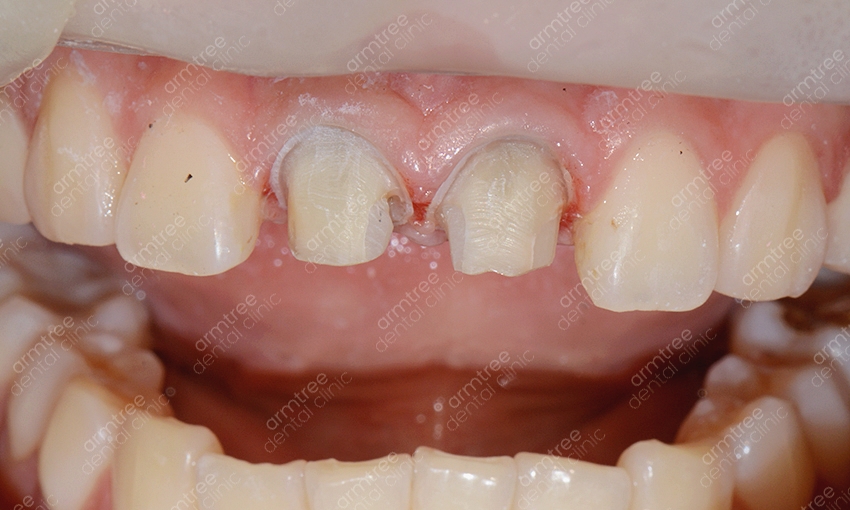

이러한 원인들과는 다른 부분으로 인한 변색도 발생하는데 바로 충격등으로 인한 외상의 경우에요. 해당 경우에는 미백 치료도 달리 해주어야 하기에 원인 파악이 그만큼 중요한 일이라고 할 수 있는 것이에요. 미백 치료 방법을 크게 나누자면 생활치미백과 실활치미백으로 구분되어져요. 생활치와 실활치는 한자어로 뜻을 풀이할 수 있는데 생활치는 신경이 살아있는 치아, 실활치는 외상이나 충치에 의해 치아 내부의 치수가 괴사한 치아를 의미해요. 치아 미백의 원리는 과산화수소나 과봉산나트륨의 약제를 치아에 적용시켜 착색물질을 산화시키는 것인데 기본 원리에는 차이가 없지만 집에서 하는 자가셀프미백은 저농도의 과산화수소를 적용하여 서서히 미백의 효과를 보는 과정이고 치과에서 진행하는 전문가미백의 경우에는 고농도의 과산화수소와 광선을 사용하여 기간을 단축시키는 과정이란 것이 차이점일수 있었어요. 실활치미백은 치아 내부에 약제를 넣어 미백을 시키는 방법이에요. 실활치 미백이 필요한 경우 치아 변색 원인에서 볼 수 있든 치아 전반에 걸쳐 착색이 이루어진 경우가 많지만 반대로 치아 하나의 변색일 경우 그 원인 파악이 중요하며 필요에 따라 신경치료를 동반해야 할 수도 있었어요. 특히 앞니 변색이 검게 나타나고 있다면 실활치에 대한 부분을 파악해봐야 하겠어요.

전문가 미백, 자가 셀프 미백 등 생활치를 미백하는 방법은 치아의 곁표면을 하얀 색상으로 바꾸어 주기 위한 과정인데 검게 변한 치아의 경우 영구치의 내부에서 발생한 문제이기 때문에 치아의 곁표면을 하얗게 만들어 주는 미백 방법으로는 효과도 미미할 뿐만 아니라 근본적인 원인을 치료하는 데에 도움이 되지 않을 수 있었어요. 따라서 검게 변한 치아에는 앞선 방법을 적용해야 옳은 방법이 되겠어요. 하나의 치아 변색이라서 통증이 없어서 방치하시는 경우도 있지만 앞니변색의 경우 하나의 치아이기에 다른 변색의 경우보다 더 두드러져보여 심미적으로 안 좋은 영향을 미칠 수 있기에 실활치미백으로 개선하는 것이 외적으로 만족도를 높혀 줄 수 있겠어요. 치아가 어둡게 변한 원인으로는 여러 사항들이 있을 수 있겠지만 치아의 신경이 괴사했다거나 구강에 따로 심어둔 충전재가 노후화된 것, 혹은 남아있는 치수 조직이 어둡게 변색이 되었을 때를 예로 들 수 있는데 이렇게 활력을 잃어 검게 변색된 치아는 시술 이후 크라운을 씌운다고 하더라도 변색된 부분이 비춰보일 수 있고 잇몸색이 변해 치아 자체가 검은 색으로 보이기도 해요. 따라서 겉면만 개선하는 방식보단 내부까지 치료를 해주어야 효과를 볼 수 있겠어요.

신논현역 치과 아름드리치과에서 실활치미백을 진행하는 과정을 알려드릴께요. 먼저 치아 내부의 신경과 혈관 등이 괴사한 경우라면 신경치료를 우선적으로 진행해요. 신경치료를 마무리 한 후 입술보호제를 꼼꼼히 발라주고 신경 쪽을 막은 뒤 미백제를 투여하는 과정을 진행해요. 충전된 미백제 입구를 막고 상태를 지켜본 뒤 간격을 두고 미백약제를 교체하여 몇 번의 과정을 반복해주어요. 물론 개인차가 존재하지만 대략 2-3회 정도 반복 과정을 한 뒤 미백이 완료되면 입구를 레진으로 수복하여 마무리를 해요. 치아미백을 하시고 난 후 외관상으로 다른 부작용은 없으나 간혹 약간의 시림증상이 발생할 수 있는데요. 하지만 일정 시간이 지나면 곧 괜찮아 지며 변색의 정도가 심해 미백으로 개선이 어려울 시 라미네이트도 대안이 될 수 있다는 걸 알아두세요. 앞니변색으로 인하여 미백을 진행할 경우 하얀 치아로 개선하는 것도 중요하겠지만 다른 치아와의 컬러 밸런스가 필요해요. 하나만 홀로 하얗다면 검거나 누런 것과 비슷하게 심미적으론 좋지 않기 때문에 색상 조절을 잘 해줄 수 있는 전문적인 의료기관을 선택해야 하겠어요.